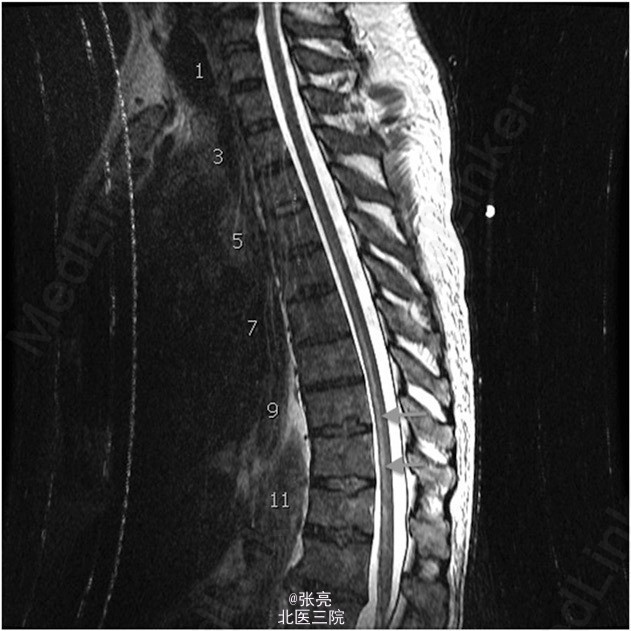

胸腔镜活检确诊为恶性胸膜间皮瘤。患者接受了四个疗程的化疗(顺铂/陪美曲塞),影像学随访显示肿瘤体积逐步缩小。超声引导内镜针吸活检纵隔淋巴结提示无转移。患者一般状态及心肺储备良好。故决定行胸膜外全肺切除术。 顺利在左侧脊柱旁T5到T6节段水平植入导管。给予患者双腔气管内插管,桡动脉和中心静脉置管。患者取右侧卧位,取左侧后外侧切口。肿瘤超出了胸膜覆盖范围,广泛侵犯主动脉周围,但主动脉和肿瘤之间界线清楚。 胸膜外全肺切除术进展顺利,整块切除了受累肺组织、纵隔淋巴结、左侧膈肌和同侧受累的局部心包膜。对T3到T6节段水平的同侧上段胸椎节段动脉进行缝合结扎及电凝切断。相应节段平面和神经管无活动性出血。 给予2 mm的聚四氟乙烯(GROE-TEX)补片修补缺损的膈肌和心包。止血良好。总出血量估计在1300 ml,输注5个单位的浓缩红细胞。术后患者转入ICU,给予小剂量0.5 mcg/kg/min的去氧肾上腺素维持血压。 到达ICU时,患者血流动力学稳定,神经功能完整。手术当晚,患者经历了两次短暂的低血压过程,每次持续不到1min,收缩压降低至60-70 mm Hg。给予输液和调整升压药剂量好有效维持血压。 第二天早晨,护士发现患者双下肢不能活动。体格检查发现双下肢瘫痪,感觉保留。MRI提示,脊髓中枢T5到T12节段水平T2异常高信号,无脊髓硬膜外血肿或脊髓压迫。这些表现与脊髓缺血相一致。 立刻给予患者改善脊髓灌注的标准治疗方案。维持平均动脉压在80mmHg,麻醉师行腰大池引流,降低脑脊液压力至10cmH2O以下。在接下来的2周中,患者下肢运动功能略有改善。但功能上仍截瘫,有大小便失禁。 术后17天,患者转入康复医院接受进一步治疗。

胸膜外全肺切除术有许多并发症,但就作者所知及文献回顾,这是首次术后出现截瘫的报道。开胸术后截瘫的报道一般与局部硬膜外出血所致脊髓压迫或由于止血剂造成的节段椎孔压缩导致的脊髓节段压迫相关。 将肿瘤从后纵隔和胸主动脉行钝性分离,可导致节段动脉或结扎部位撕裂。脊髓灌注取决于对侧完整的节段动脉血供和低位胸椎水平Adamkiewicz动脉的完整。脊髓前角缺血好发部位是在T9到T12节段水平,往往是由于Adamkiewicz动脉区域性缺血所造成。 本文报道了一个罕见的高位脊髓前角缺血,根据MRI推测很可能是由于脊髓中段血管解剖变异所造成。虽然患者术后经历了两次短暂的低血压发生,但是脊髓灌注不良才是造成患者术后截瘫的最可能原因。 对于此类患者需关注这一之前未报道的罕见并发症。应告知患者及其家属这一重要并发症及其可能的风险。